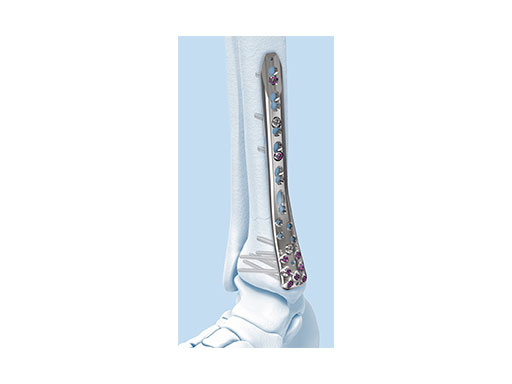

The Combi holes in the Variable Angle LCP plate shaft combine a dynamic compression unit hole with a variable angle locking screw hole. Due to the smaller sized and more numerous fixation options distally with 2.7 mm VA screws, the fixed-angle construct provides advantages for small metaphyseal segments where traditional screw fixation can be limited. The screw trajectories are optimized to support the distal articular surface. The multiple variable angle locking holes in the plate head accept 2.7 mm VA locking, 2.7 mm locking, 2.7 mm cortex, and 2.7 mm metaphyseal screws. The latter has a low profile screw head to avoid soft tissue irritations and can be used to pull the plate to the bone. Due to the numerous screw possibilities, it is important that the surgeon is familiar with which screws can be used in which plate holes. The system includes guide blocks for all plates (except T and L plates) for inserting screws in the plate head at nominal screw angles (Fig 1a-c). K-wire holes in the plate head and shaft tip accept K-wires up to 1.6 mm. They can be used to temporarily reduce articular fragments, and to confirm the location of the plate relative to the distal tibia and fibula.